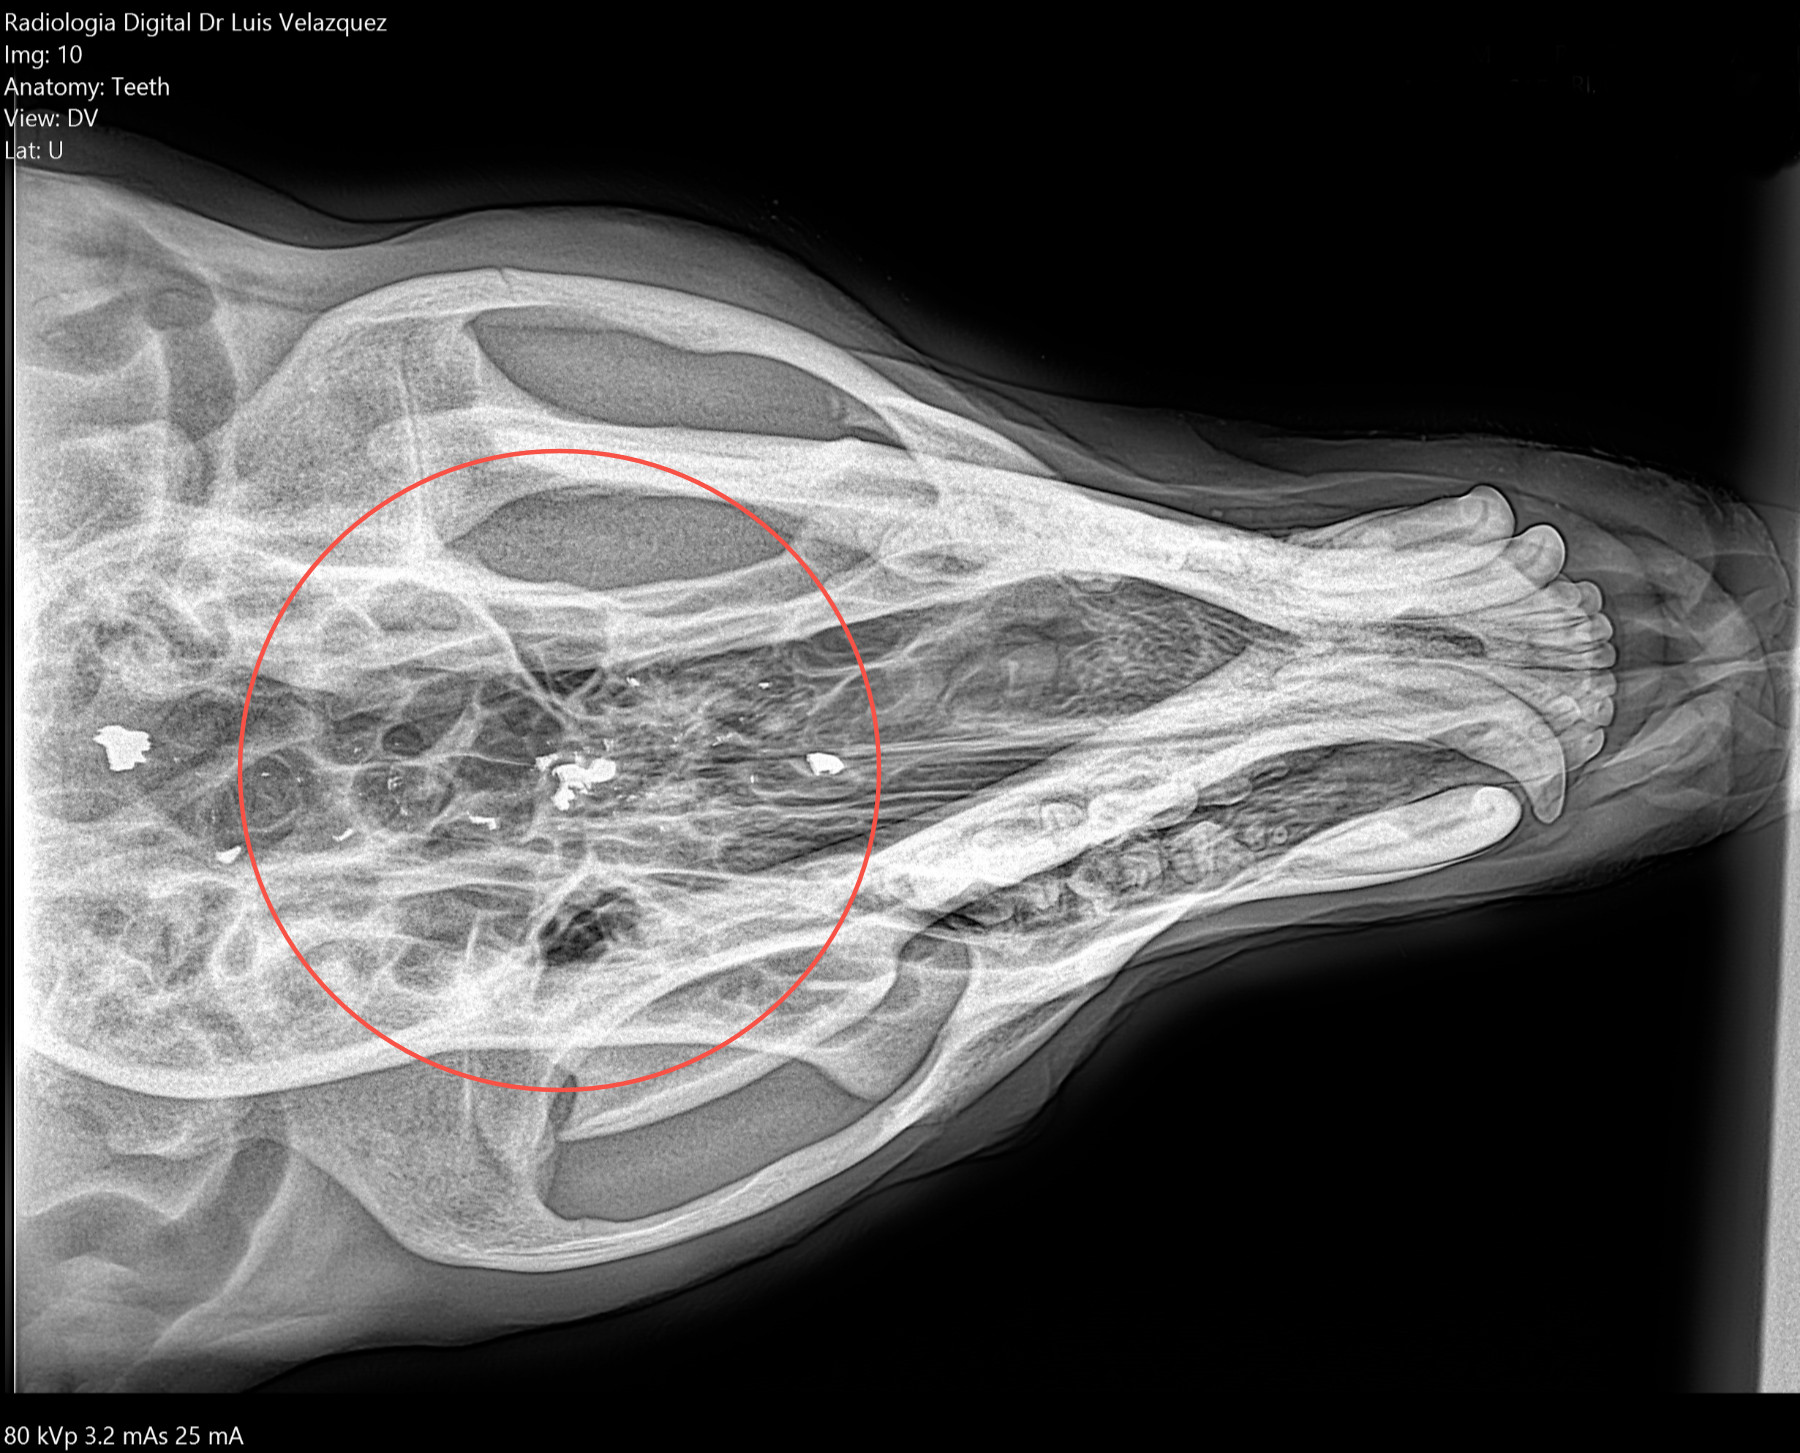

Radiología Digital como Herramienta Complementaria en el Dictamen de Bienes Muebles

Desde el descubrimiento de los rayos “X” y las placas radiográficas por Wilhelm Conrad Roentgen y su posterior difusión a través de la Asociación Físico médica de Wurzburg el 28 de diciembre de 1895, que fue la primera asociación que habló de los nuevos rayos que podían penetrar el cuerpo y fotografiar los huesos, ha habido muchos cambios tanto en la forma de obtener, procesar e incluso en la forma de visualizar, manejar y almacenar las placas radiográficas.